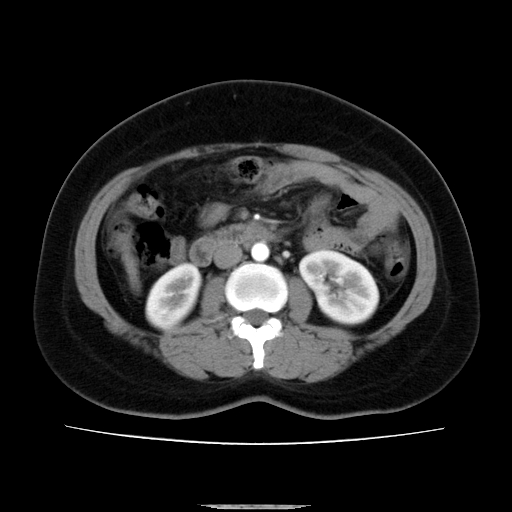

标题: CT14225:女性46岁。当地B超示肝内占位,来我院作CT检查。请 [打印本页]

标题: CT14225:女性46岁。当地B超示肝内占位,来我院作CT检查。请

肝内结节强化特点符合原发性肝癌表现,脾脏改变考虑为增大及先天发育所致。

动脉期病原灶明显强化高于肝密度且中央有无强化区,静脉期强化程度下降明显,延迟低于肝密度,考虑肝腺瘤可能性大,

肝内结节强化特点:快进快出符合原发性肝癌表现

此患者虽然符合快进的特点,却不符合快出的特点,因为门脉期几乎是等密度,不符合肝癌的增强表现,所以我考虑肝局灶性结节增生可能性大